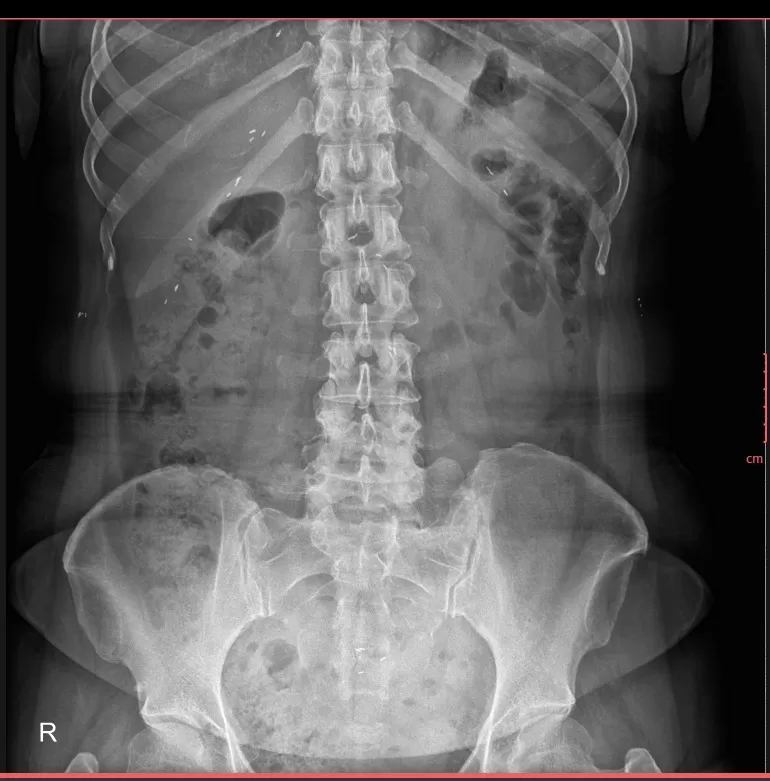

📸 Hình ảnh X-quang thường quy (đính kèm) cho thấy:

-

Nhiều nốt cản quang nhỏ, hình dạng thoi/hạt gạo,

Phân bố rải rác trong mô mềm và các khối cơ vùng ngực, bụng và thành bụng,

Các tổn thương không liên quan đến cấu trúc xương khớp.

➡️ Đây là hình ảnh điển hình gợi ý nhiễm ký sinh trùng dạng kén, đặc biệt là kén sán, một bệnh lý dễ bị chẩn đoán nhầm do triệu chứng lâm sàng không đặc hiệu.